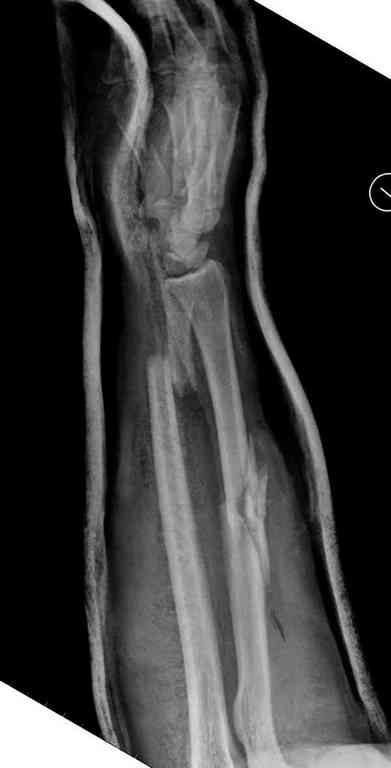

Множественная огнестрельная травма конечностей, перелом костей предплечья, фиксация в первые часы и дефект мягких тканей, мероприятия по закрытию...

Имя     : 1 GSW forearm.jpg

Тип     : image/jpeg

Размер  : 20610 байтов

Url     : http://weborto.net:8080/pipermail/ortho/attachments/20100808/dab7f922/attachment-0010.jpg